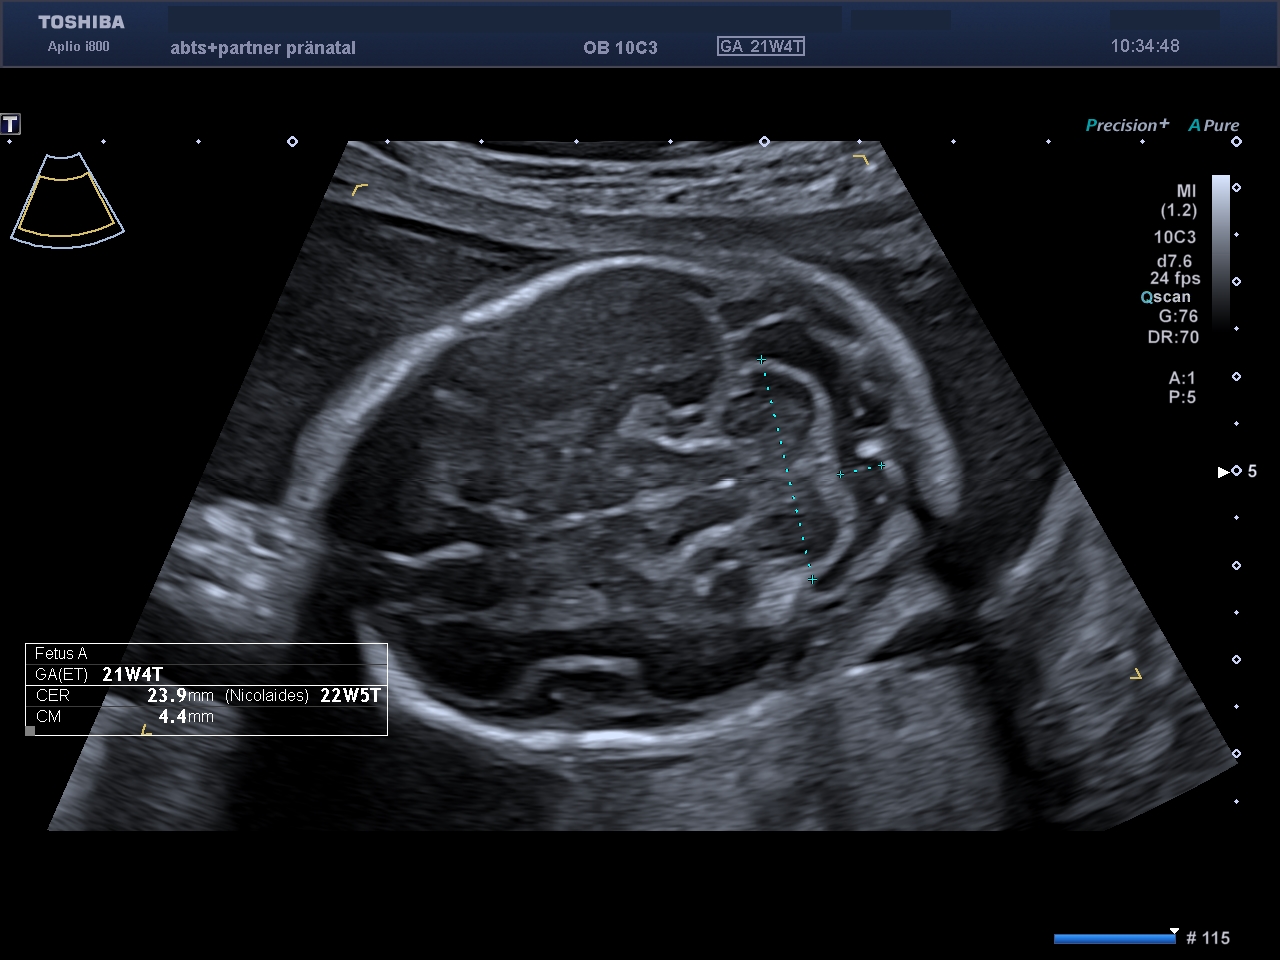

Kopfform und Großhirnhälften sind unauffällig entwickelt.

Das kindliche Herz zeigt normale Anatomie und unauffälliges Blutflussmuster.

Der kindliche Bauchumfang mit dem gefüllten Magen.